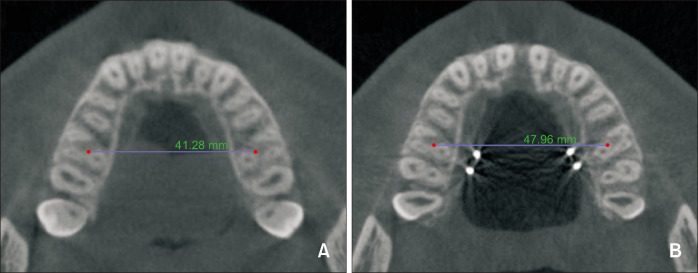

Methods: Cone-beam computed tomography images were obtained from a total of 60 patients both before expansion (T1) and 3 to 6 months after expansion (T2). Measurements taken included tooth length, root length, crown length and center of resistance. Resorption length (RL) and resorption length percentage (RLp), resorption volume (RV) and resorption volume percentage (RVp) and the amount of expansion were calculated.

Abstract Image